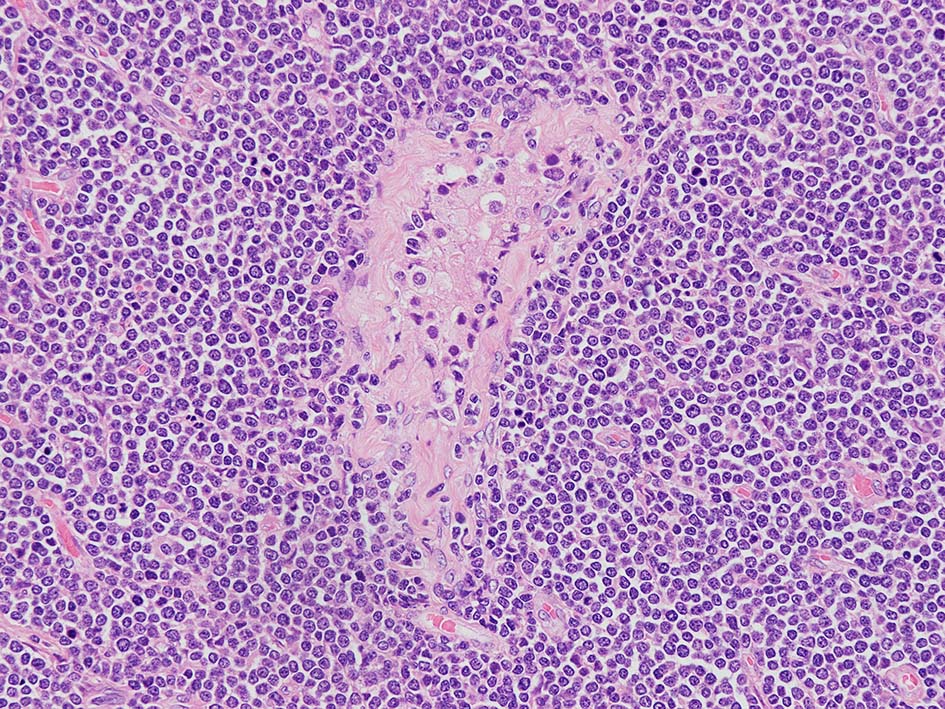

loupe像Aの領域: 精細管をスペアするように, 小型リンパ球優位, 一部中型のlymphoid cellsがシート状密に浸潤増殖する. tubulesのほとんどにはlymphoid cellsが浸潤していないが, LELに似たようなlympho-tubular lesionが少数認められた. x400高倍率では, 増殖細胞は, 粗く, 凝集したクロマチンをもつ類円形, non-cleavedな核をもつ細胞質の乏しいlymphoid cellsである. 核小体か凝集したクロマチンかわかりにくい.

白膜には密に腫瘍性リンパ球が浸潤増殖し, 肥厚, 一部は上図loupe像のように, 腫瘤を形成している. 浸潤リンパ球は精巣実質内よりも, やや大きく, 多稜形, くびれのある核をもち, クロマチンは淡明で核小体が明瞭になってきている.

骨髄切片/組織では、リンパ芽球細胞は, 高N:C比、薄い核膜、細かい点状のクロマチンを示し、核小体は目立たない. mitosisの数はB-ALLよりもT-ALLが多いと報告されている.

T-ALLでは, T-LBLでは、一般にリンパ節の構築物が完全に消失し、被膜に浸潤していることが確認されます。 副皮質に部分的に病変が生じ、胚中心が温存されることもあります。時に、線維性骨格の伸展により、濾胞性リンパ腫に類似した多結節性パターンが生じることがある。 T-LBLでは核小体や細胞質はあまり目立たないが、星空効果が見られ、バーキットリンパ腫を模倣することがある。 芽球の核は丸いものと畳み込まれたものがある。有糸分裂図形はしばしば多数存在する。 胸腺では、胸腺実質の広範な置換と周囲の線維脂肪組織への浸透性浸潤が見られる。